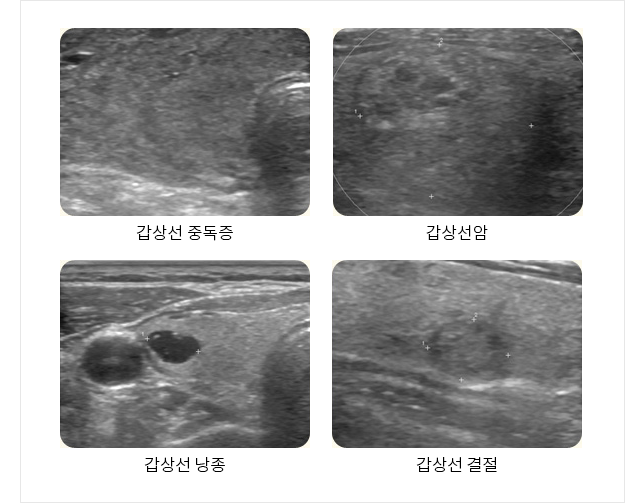

복부 초음파, 간섬유화 검사 갑상선, 유방 초음파 경동맥 초음파 관절 초음파